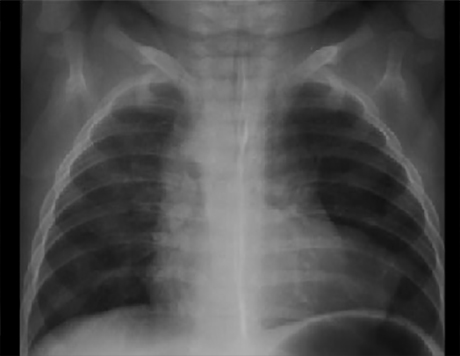

You are incorrect - the best interpretation of the chest X ray in our patient is RV enlargement + small pulmonary trunk + ↓ pulmonary arterial vascularity + right Ao arch.

This chest X ray taken during a barium swallow shows right biventricular enlargement, obscure pulmonary trunk, increased pulmonary vascularity and a right aortic arch.

Biventricular enlargement is reflected by the large cardiac shadow extending both leftward and rightward. The pulmonary trunk shadow is not clearly seen, but is not obviously absent. Increased pulmonary arterial vascularity is reflected by dilated central pulmonary arteries and prominent distal arterial vascular markings. A right aortic arch is suggested by a shift of the tracheal air shadow to the left, caused by the arch passing to its right, as well as aortic knob and descending aorta seen at the upper right mediastinal shadow.